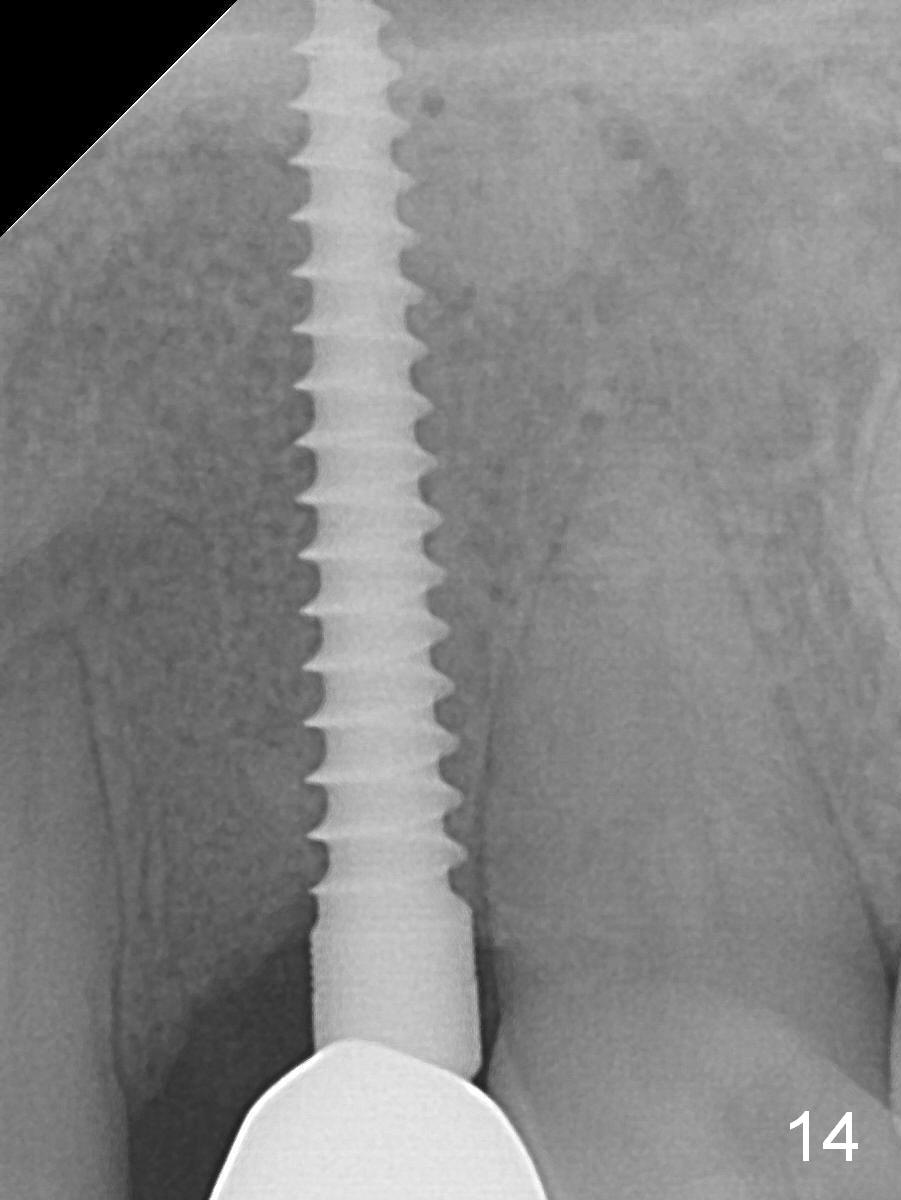

There is no gingival recesssion (data not shown) or bone loss around the implant 1 year post cementation (1 year 9 months postop; Fig.14).